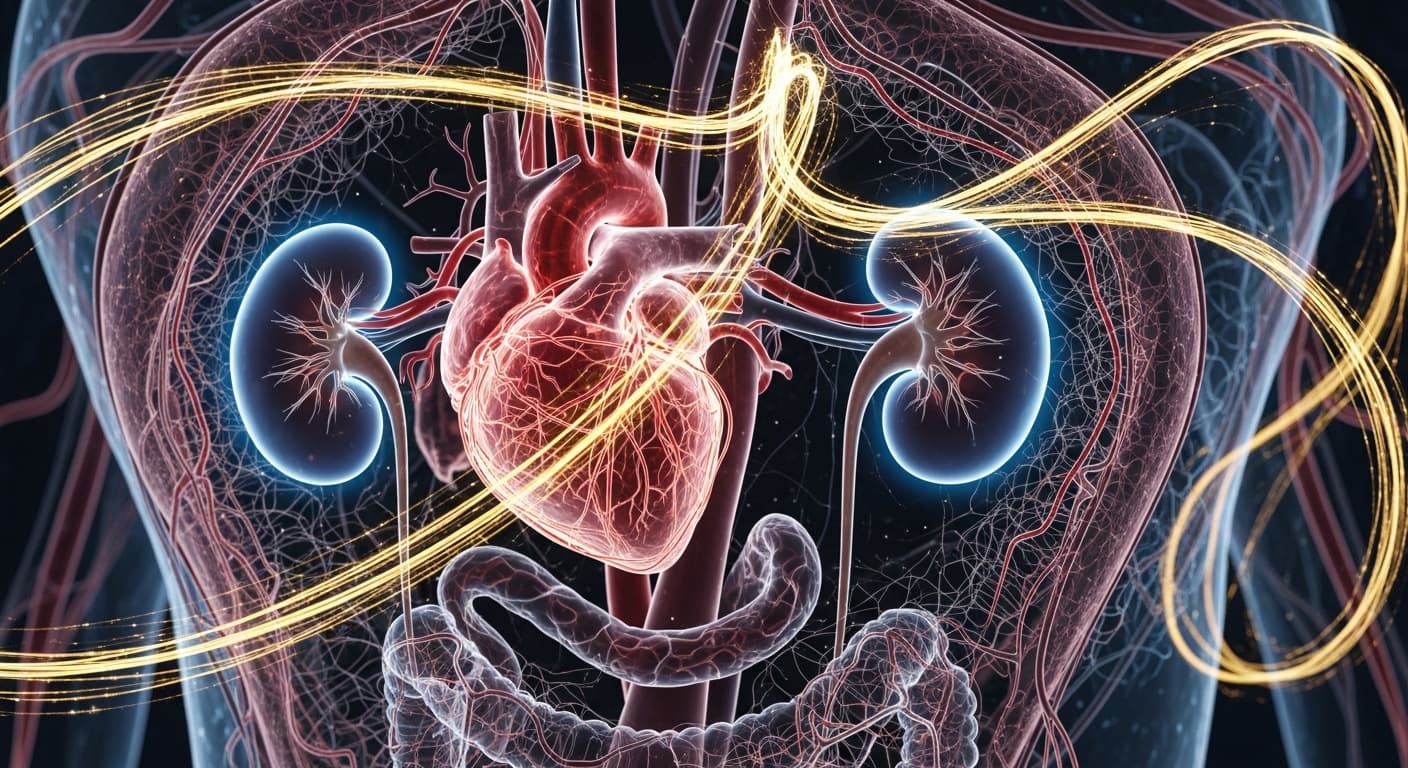

현대 의학은 귀에서 심장 박동 소리가 들리는 현상을 '박동성 이명(Pulsatile Tinnitus)'이라 정의하고 매우 중요한 증상으로 간주합니다. 이 소리는 단순히 스트레스나 피로로 인한 일시적인 증상이 아니라, 귀 주변을 지나가는 혈관의 이상이나 전신 질환의 신호일 가능성이 높기 때문이에요. 귀 주변에는 수많은 혈관들이 복잡하게 얽혀 있어, 이곳을 흐르는 혈액의 소리가 비정상적으로 커지거나 혈관 자체에 문제가 생겼을 때 박동성 이명이 발생할 수 있습니다. 가장 흔한 원인 중 하나는 '고혈압'입니다. 혈압이 높으면 혈액이 흐르는 속도와 압력이 강해져, 평소에는 들리지 않던 혈류음이 귀 속 민감한 구조물에 직접적으로 전달될 수 있어요. 마치 오래된 수도관에 수압이 너무 세게 걸리면 덜컹거리는 소리가 나는 것과 비슷하죠. 이는 꾸준한 혈압 관리가 필요한 신호일 수 있습니다. 또 다른 심각한 원인으로는 동맥경화로 인한 '경동맥 협착', 혈관벽이 부풀어 오르는 '동맥류(Aneurysm)', 선천적인 '혈관 기형(Arteriovenous Malformation, AVM)' 등이 있습니다. 이러한 구조적인 혈관 이상은 뇌로 가는 혈액 흐름에 영향을 주어 귀 주변 혈관의 소리를 증폭시키거나, 혈액이 휘몰아치는 난류(turbulence)를 유발해 맥박과 같은 소리를 만들어낼 수 있어요. 특히 동맥류나 혈관 기형은 자칫 뇌출혈 같은 치명적인 상황으로 이어질 수 있어 즉각적인 진단과 치료가 필수적입니다. 이 외에도 '빈혈'이나 '갑상선 기능 항진증'처럼 혈액 순환 자체가 빨라지거나 심박수가 증가하는 전신 질환도 박동성 이명의 원인이 될 수 있습니다. 혈액의 점도가 낮아져 혈류 소리가 더 잘 들리거나, 심장이 과도하게 박동하면서 발생하는 것이죠. 드물게는 '특발성 두개내압 상승(Idiopathic Intracranial Hypertension)'과 같이 뇌압이 높아져 뇌 주변 혈관에 압력이 가해지면서 맥박성 이명을 유발하는 경우도 있습니다. 이러한 증상이 나타난다면, 단순한 이비인후과 진료를 넘어 신경과, 심장내과 등 여러 진료과와의 협진이 필요할 수 있으며, 뇌 MRI, MRA, CT 혈관조영술 등을 통해 혈관의 구조적 이상 유무를 확인하는 것이 매우 중요합니다. 이 소리는 단순히 귀찮은 소음이 아니라, 뇌혈관 질환이나 심각한 내과적 질환의 초기 경고음일 수 있기 때문에 절대 가볍게 넘겨서는 안 돼요. 반드시 전문가의 정확한 진단과 치료를 받아야 합니다.